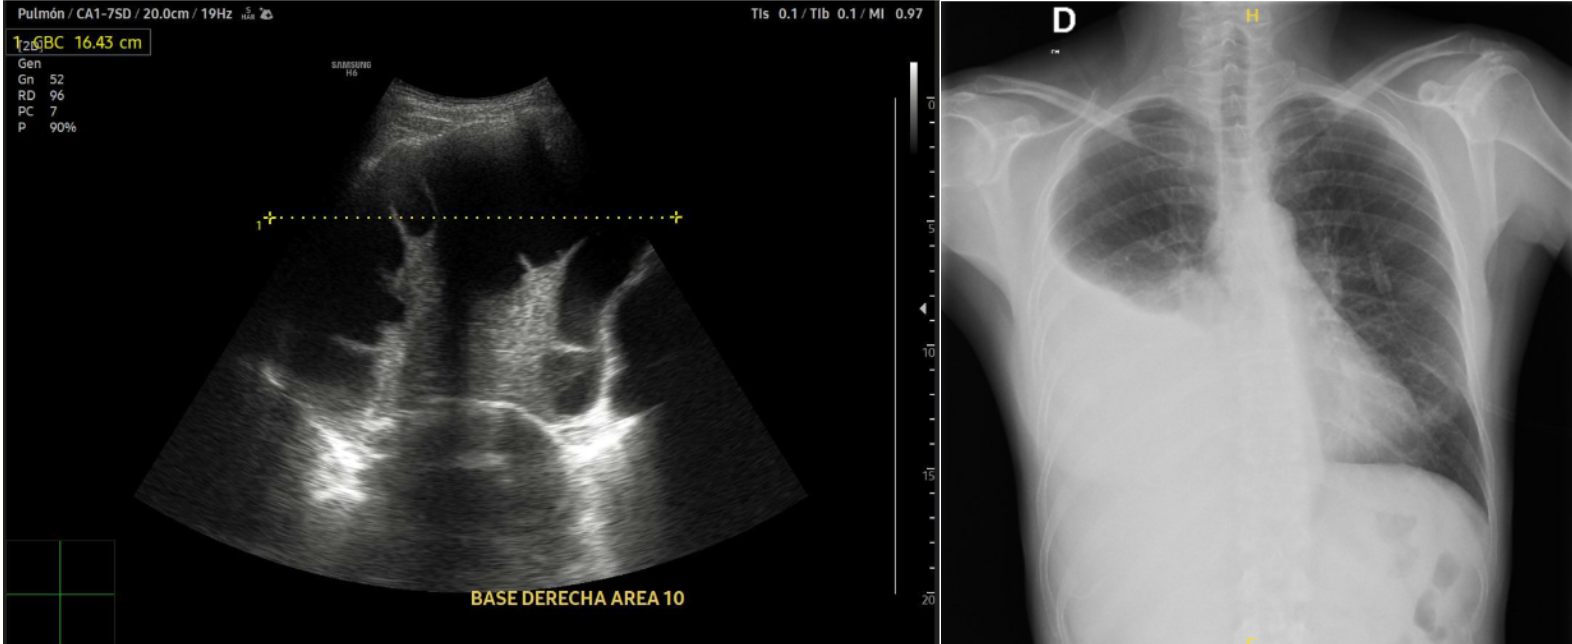

Afebril, Taquicárdica a 114 latidos/minuto, Hipertensa 184/91 mmHg, Saturación oxígeno 91%. Auscultación cardio/respiratoria: rítmica sin soplos, Hipofonesis pulmonar base derecha.

Realizamos Ecografía clínica pulmonar: imagen anecoica con septos finos y signo de la medusa compatible con derrame pleural tabicado con atelectasia en base derecha de aproximadamente 1150 ml por cuantificación de Goecke 2, en ápex líneas B finas. Campo pulmonar izquierdo líneas A.

En urgencias hospitalarias: Dímero D 1400 , sin leucocitosis, Radiografía de tórax derrame pleural derecho, Angiografía pulmonar: descarta TEP. Moderado/severo derrame pleural derecho con atelectasia pasiva.